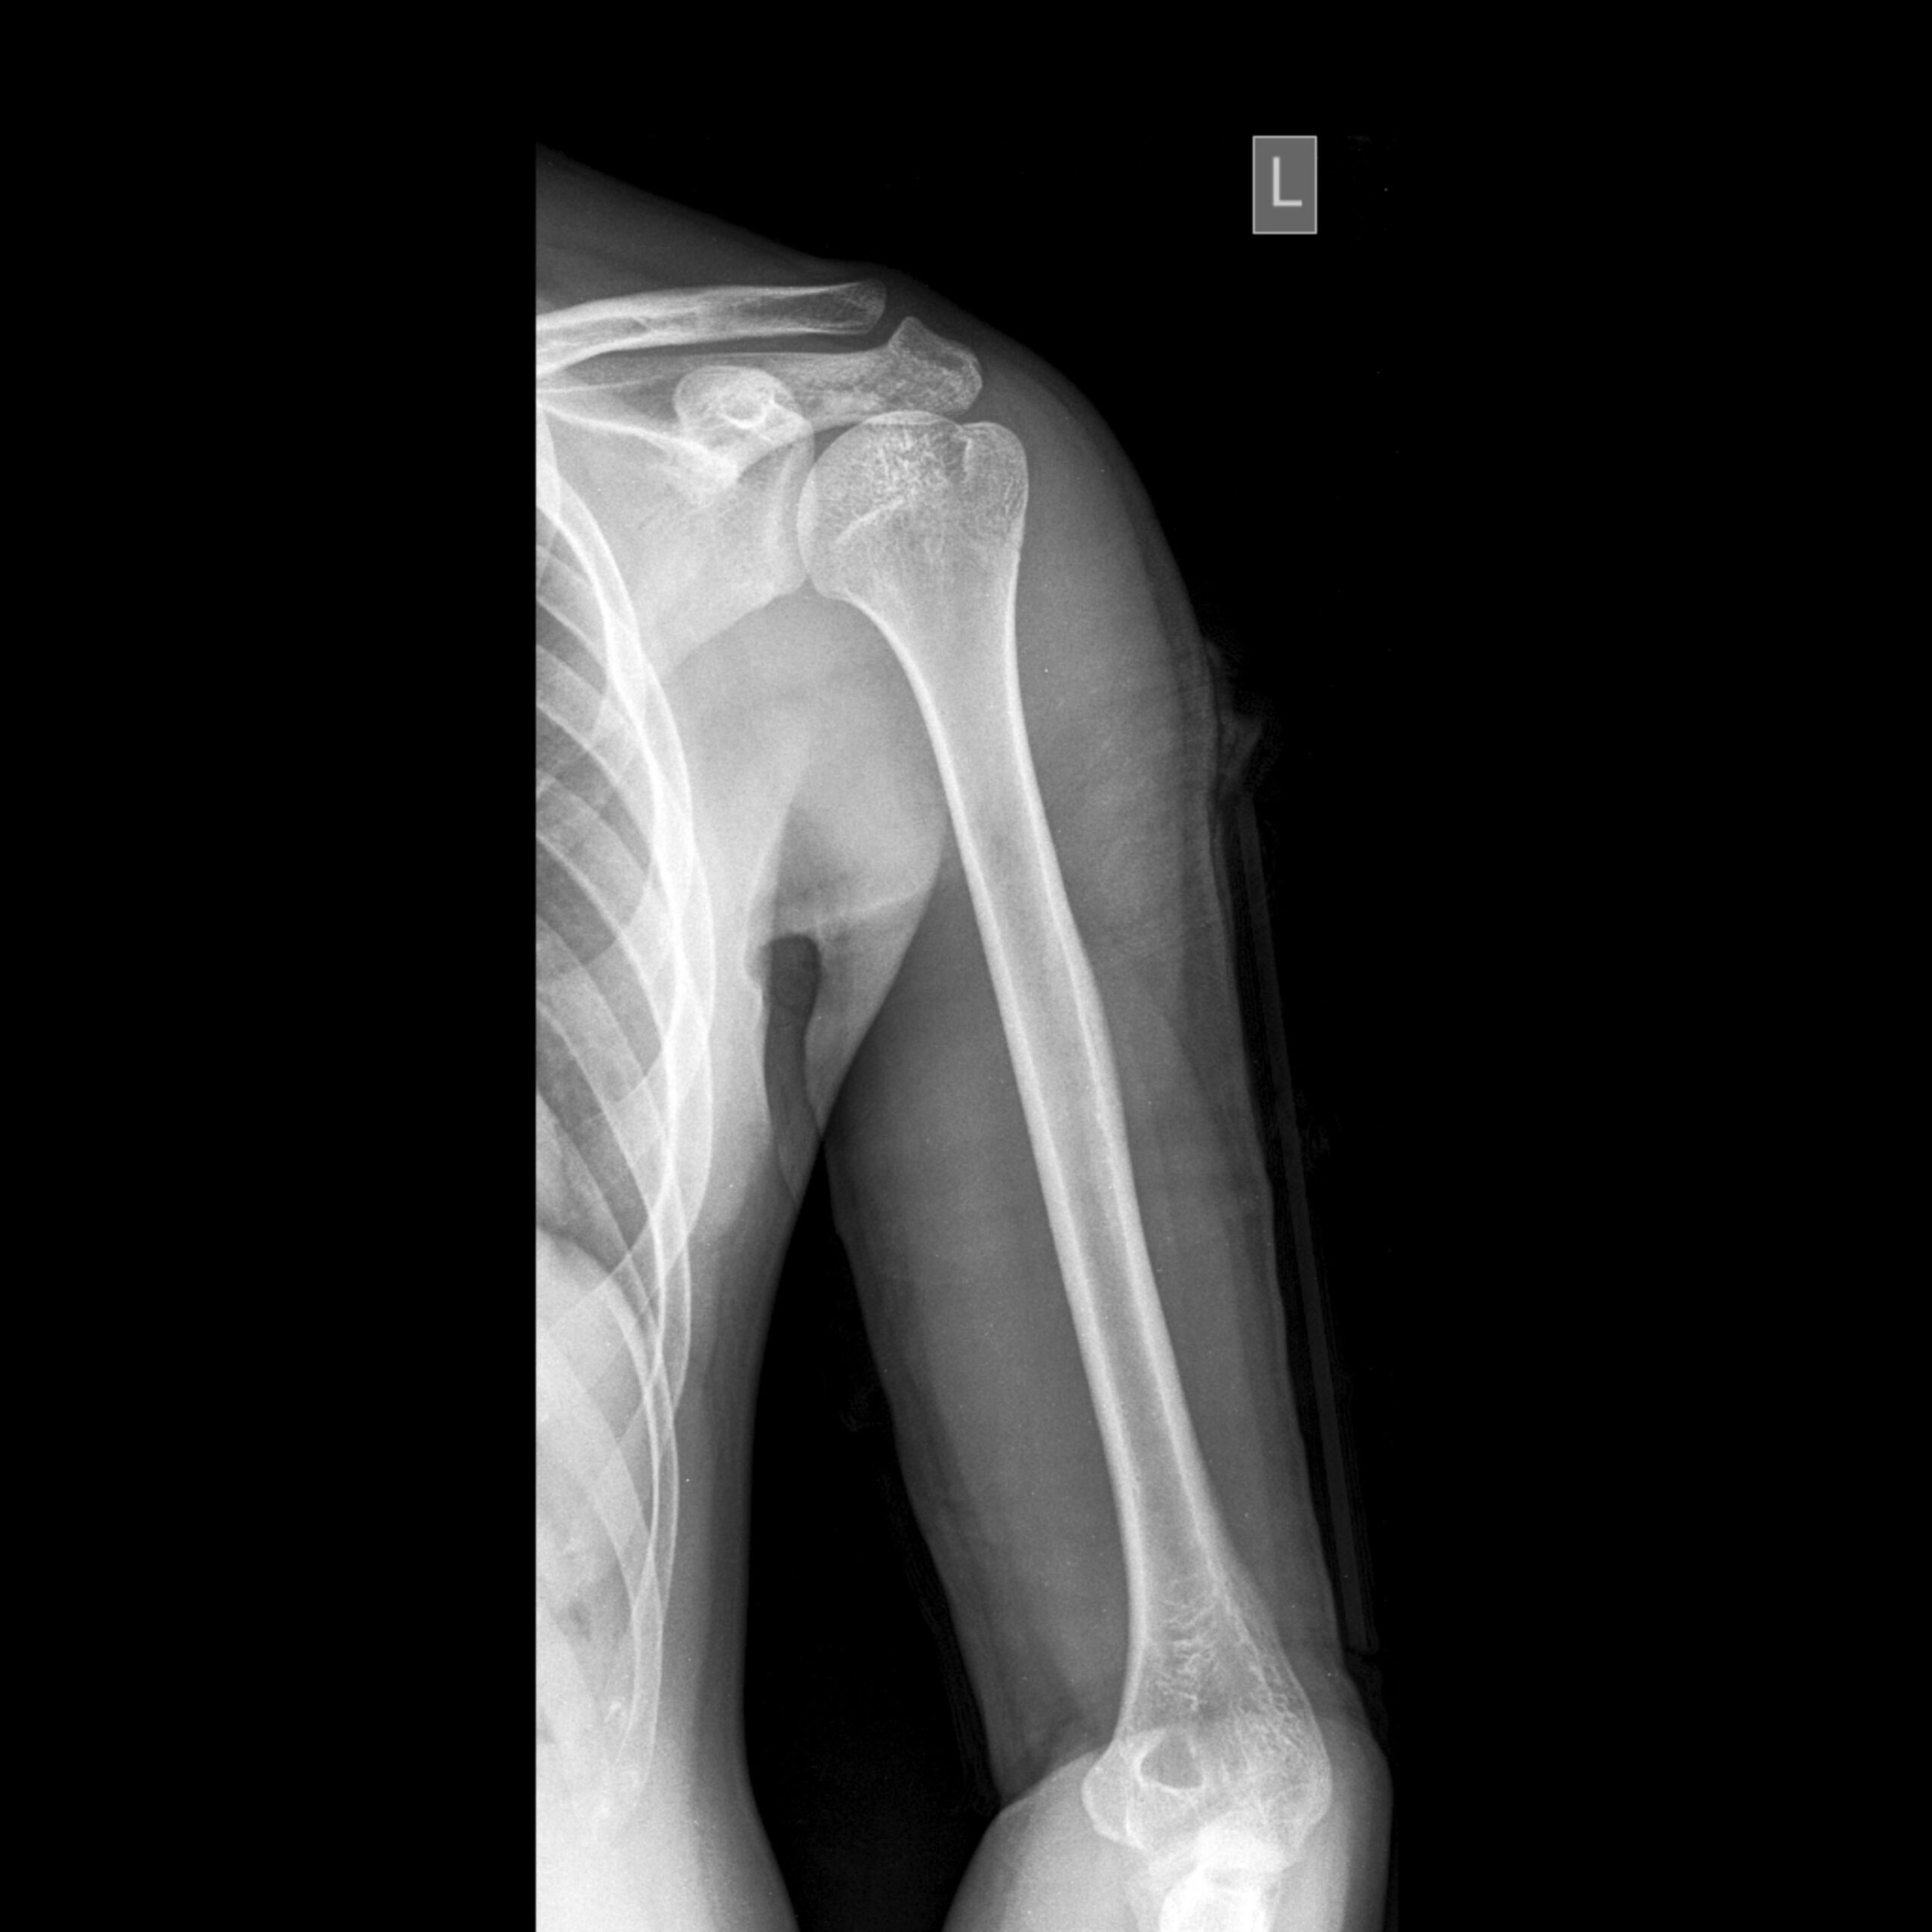

The AP (Anteroposterior) View of the Humerus is a standard X-ray projection used to visualize the entire length of the humerus, from the shoulder to the elbow. In this view, the patient typically stands or sits with the arm fully extended and supinated (palm facing forward), and the X-ray beam passes from front (anterior) to back (posterior), centered on the midshaft of the humerus. This positioning provides a clear, undistorted image of the humeral shaft, head, neck, and both proximal and distal joints (shoulder and elbow), allowing assessment of fractures, dislocations, bone lesions, or alignment abnormalities. The AP view is often complemented by a lateral or oblique projection for a comprehensive evaluation.

AP view